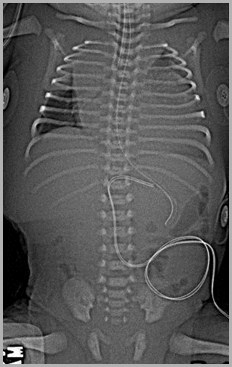

UAC too high at T4Umbilical Venous Catheter passes thru foramen ovale into left atrium andleft pulmonary vein

4